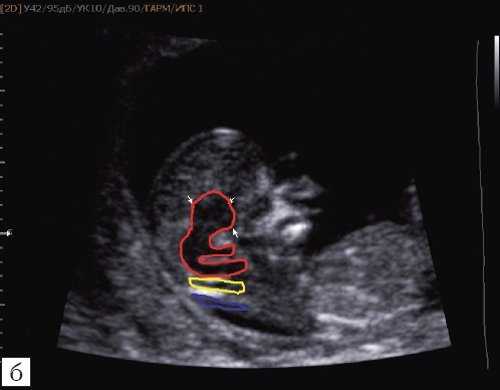

При изучении анатомии головного мозга плода в режиме 2D с применением стандартных аксиальных срезов во всех наших случаях мозжечок выглядел в виде овального образования однородной структуры с поперечным размером, менее уровня 5 процентиля для соответствующего срока беременности. При этом отсутствовала межполушарная выемка и область повышенной эхогенности по срединной линии мозжечка, характерная для отражения червя (рис. 1). На коронарном срезе также обращала внимание округлая однолобарная форма гипоэхогенного мозжечка (рис. 2). Использование трансвагинального подхода позволяло визуализировать дополнительно волокнистые структуры субарахноидального пространства (рис. 2).

Рис. 1. Аксиальные срезы головного мозга плода. Отражена картина однолобарного гипоплазированного мозжечка во всех наблюдениях.

а) Наблюдение 1.

б) Наблюдение 2.

Рис. 2. Корональные срезы головного мозга плода. Показан овальный контур мозжечка и волокнистые структуры субарахноидального пространства (стрелки).

а) Наблюдение 1, 3D.

б) Наблюдение 4, трансвагинально.